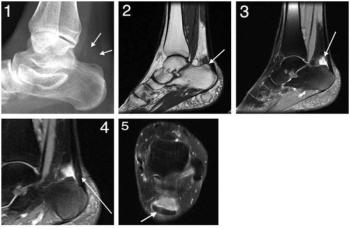

A 51-year-old woman presented to the clinic complaining of left heel pain.Tenderness and soft tissue swelling were observed. MRI reveals Haglund's deformity.